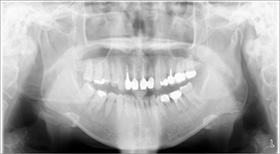

經X光片發現牙齒底部病變,評估建議立即拔牙且立即植牙